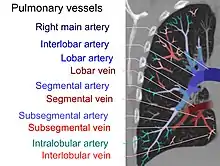

On CTPA, the pulmonary vessels are filled with contrast, and appear white. Any mass filling defects (embolus or other matter such as fat) appears darker. Ideally, the scan should be complete before the contrast reaches the left side of the heart and the aorta, as this may mean contrast has drained from the pulmonary arteries, or require a larger dose of contrast media.[12]

Other from assessing any filing defect within the pulmonary trunk and its segmental branches, the diameter of the right heart can be compared with diameter of the left heart. The right heart diameter should not be more than the diameter of left heart. Normally, the interventricular septum should mildly bulge into the right ventricle due to high pressure within the left ventricle. Any reverse bulge or flattening of the interventricular septum indicates pulmonary hypertension.[12]